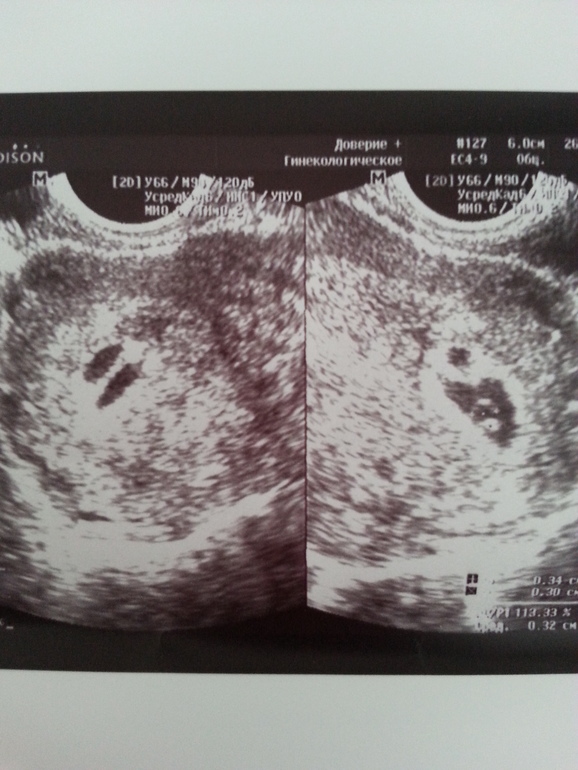

Многоплодная беременностьДевочки, сегодня первый раз была на узи и к удивлению увидели 2 плодных яйца. Задержка 2 недели, от месячных 6 недель получается срок.Только вот в одном (9.5мм) есть эмбриончик ктр 3 мм, желт.мешок 3.4 мм. А в другом нет и желт.мешка второго тоже нет, размер 5.5 мм, почти в 2 раза меньше. По опыту у кого было, что с такой разницей в показателях в итоге развилась многоплодная беременность?